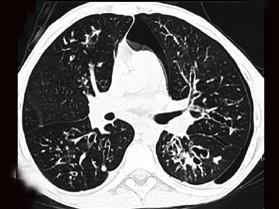

问题 男,38岁,咳嗽、咳痰、咯血,结核菌素实验(-),结合CT图像,最可能的诊断是 ( )

选项 A、间质性肺炎 B、特发性肺间质纤维化 C、肺囊虫病 D、肺囊肿 E、支气管扩张

答案 E